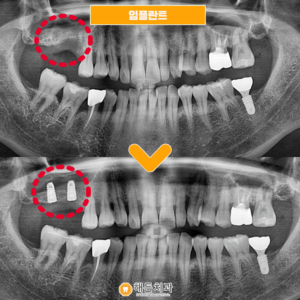

아산시치과 뼈이식을 병행하여 . 치아는 각각의 위치에 따라 역할과 기능이 다른데요. 그 중에서도 어금니는 저작기능을 집중적으로 담당하여, 음식을 맷돌처럼 잘게 부수어 소화를 돕고 있습니다. . 하지만 외상이나 사고, 또는 관리를…

아산시치과 뼈이식을 병행하여